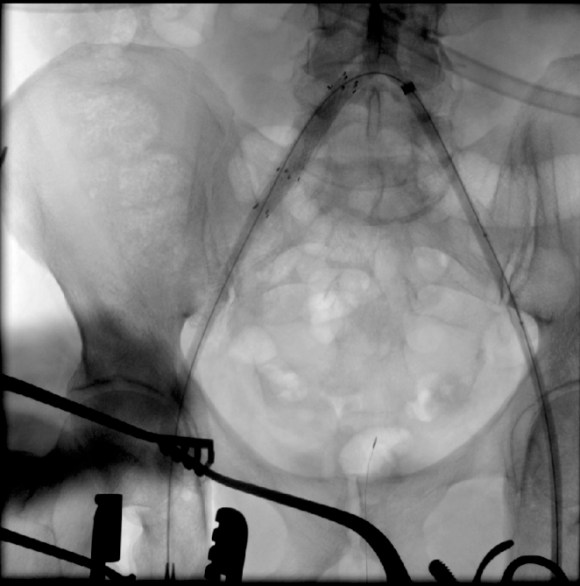

The plaque came out easily (first image, top).The proximal and distal end points required stents.

The patient regained palpable dorsalis pedis and posterior tibial artery pulses. Total OR time was less than 2 hours. An ilioinguinal field block allowed for good pain control and the patient was discharged the next morning, having to heal only a 10cm wound. There is no good endovascular option for common femoral disease, and while stenting the whole SFA can be done, on more than a few occasions I have had to treat occluded “full metal jacket” SFA stents, usually by removing them. EndoRE has been shown to be superior to PTFE and almost as good as vein in the REVAS Trial when compared to fem-AK POP bypass. Going home the next day after such an extensive revascularization is not a stunt -it’s the direct result of limiting the incision and blood loss and OR time.